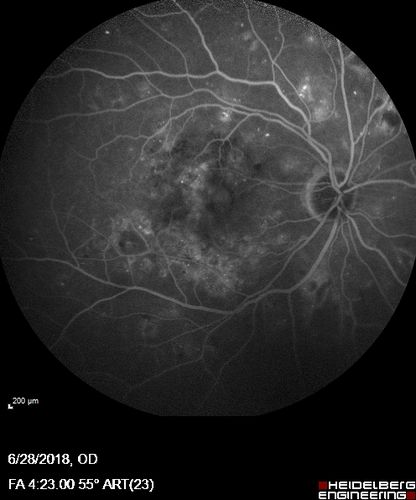

Diabetic Macular Edema with Exudates

Patient did not want injection therapy and did well with laser